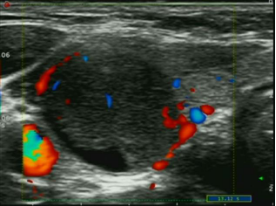

科室现开展超声项目有消化系统、泌尿系统、妇产等常规超声检查、外周血管、小器官、新生儿颅内超声检查、超声心动图检查、产科II级超声筛查(早孕、中孕)、肌骨超声、盆底超声、介入性超声(开展肝脏等多部位实体肿瘤消融术;肝、肾、盆腔等囊肿穿刺硬化治疗术;各类脓肿穿刺引流术;PTCD术;甲状腺、乳腺、前列腺、肝、肺、淋巴结等穿刺活检;肝脏、肾脏、甲状腺、乳腺等肿瘤超声造影;子宫输卵管超声造影等),其中介入性超声是我科的特色项目,清远地区率先开展的科室。近年来科室开展多项新技术、新项目,获英德市科学技术进步二等奖1项。在国家级期刊或省内期刊发表多篇论文;承担多个医学院学生的实习、带教及英德地区乡镇卫生院医师的进修学习工作。

超声引导下经皮经肝胆囊穿刺置管引流术 超声引导下颈部肿物穿刺活检术 超声引导下肝肿瘤微波消融术